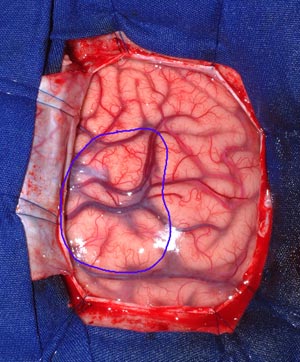

Muitas cirurgias ressectivas dessa série foram realizadas com o auxílio de eletrocorticografia intra-operatória (Figura 59).

Figura 59 - Fotografia mostrando o uso de eletrocorticografia intra-operatória.